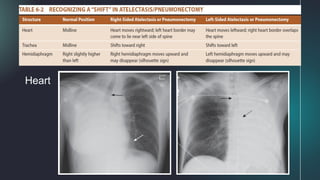

*Toward the atelectasis

Increase in the density

of the affected lung

Displacement of the

interlobar fissures

Trachea

Heart

Hemidiaphragm

Overinflation of unaffected ipsilateral lobe or

contralateral lung